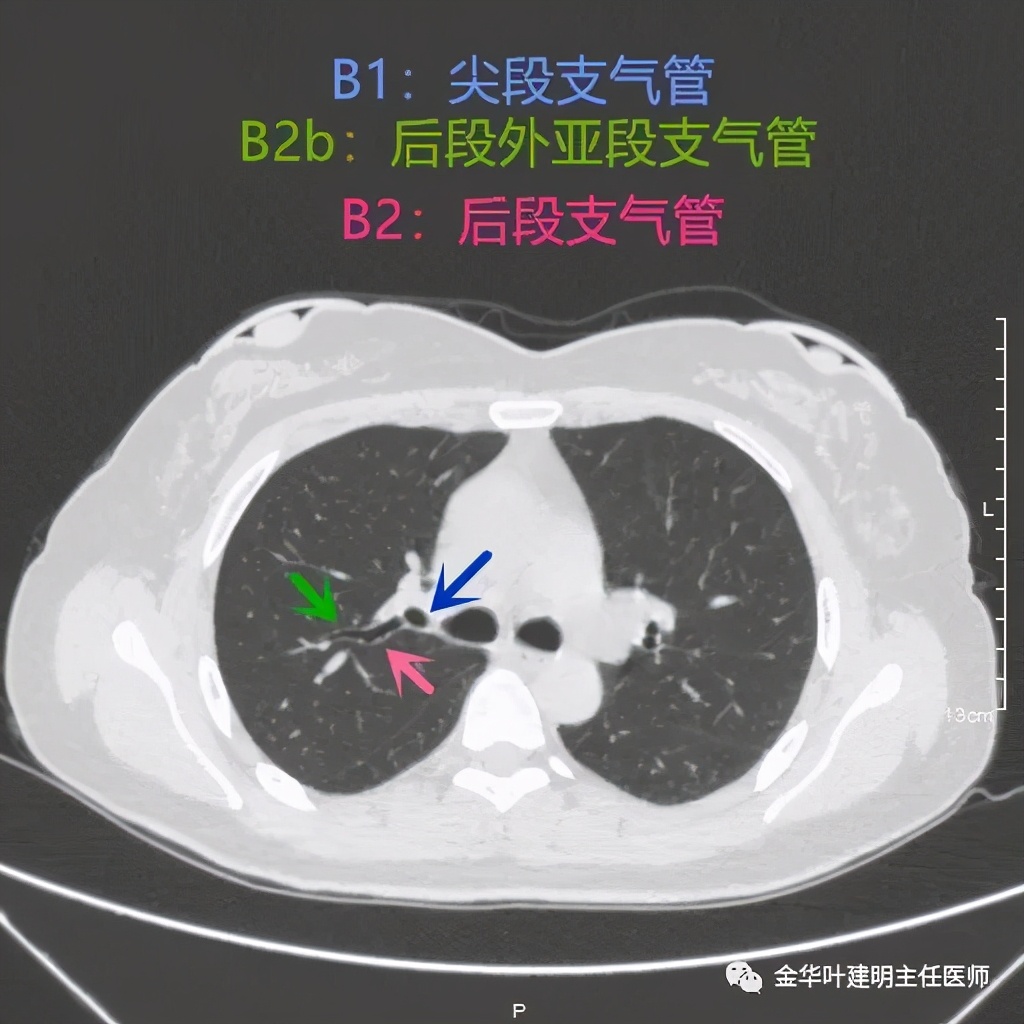

上图红色箭头所指是后段后亚段,而绿色箭头所指是后段外亚段支气管的走行,显示了两亚段的分叉处

上图显示的是后段与尖段支气管开口处,蓝色箭头所指是尖段支气管开口,粉红色箭头示后段支气管,绿色箭头示后段外亚段支气管的走行。